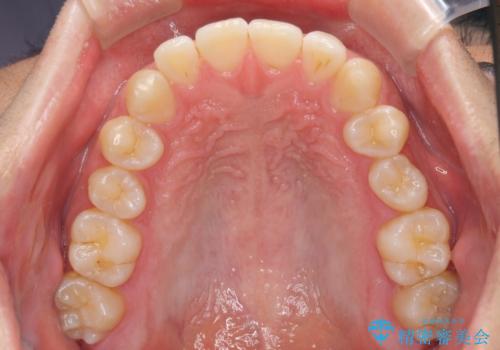

前歯のデコボコと突出感 インビザラインにて矯正治療

- 上下前歯のデコボコを気にして来院された患者様です。

インビザラインによる上下歯列の側方拡大と後方移動、IPR(歯と歯の間を削る)にるスペースの獲得により歯列を整えることとしました。

左上の小臼歯は捻転が強く、あえて180逆向きの状態で終了させる治療計画としました。

ご自宅と職場がともに遠方であったため、治療期間は長くなりましたが、患者様も我々も期待して以上に口元の突出感を改善することができました。